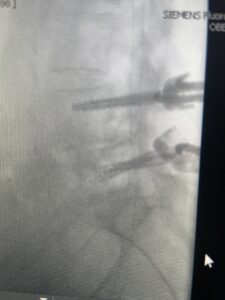

Fig 3: Lateral and AP fluoroscopic images demonstrating placement of pedicle screws for L4-5 fusion for spondylolisthesis.

This 73 year-old female had a long history of low back pain and left thigh pain and heaviness of her legs when she ambulated or did activities. She failed all means of conservative treatment including epidurals and PT. On exam she had mild weakness of her left quad but otherwise was intact. Lumbar MRI (Fig 1) revealed significant L4-5 lumbar stenosis and a grade 1-2 spondylolisthesis. Her main pathology was severe, thickened “knobs” of ligamentum forming at the posterior margin of the superior facet processes of L5 and lamina (Fig 2). The patient underwent a decompressive laminectomy of L4 as well as removal of the inferior processes of L5 to widely decompress bilaterally the L4 and L5 nerve roots. Intraoperatively, the descending L5 nerve roots were compressed severely by this severe thickened ligamentum in the subarticular recess. Because of the significant spondylolisthesis we augmented her decompression with fusion. She underwent an L4-5 posterolateral fusion with segmental instrumentation (Fig 3)). Postoperatively she had an uneventful course with relief of her leg pain.